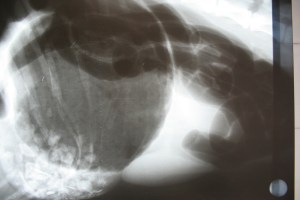

Ayer llegó Tom, un perrito de 12 años que llevaba 3 días con vómitos. Las radiografías mostraban un cuerpo extraño en el estómago. Después de estabilizarlo, hidratarlo y hacer el preoperatorio, le hemos extraído mediante una gastrotomía (hacer una incisión en el estómago) el amasijo de ramas, hojas y hierbas y pensábamos que ya estaba todo hecho. Gracias a nuestros protocolos, que en este caso consiste en revisar SIEMPRE el abdomen antes de cerrar, hemos encontrado un segundo cuerpo extraño: un botón grande, muy bonito, pero que obstruía el yeyuno (intestino delgado). Hemos necesitado una enterotomía (hacer una incisión en el intestino, y cerrarla después) para solucionar el segundo problema y que obstruía el tránsito intestinal. Tom se recupera bien de su cirugía, y esperamos que en una semana le daremos el alta.